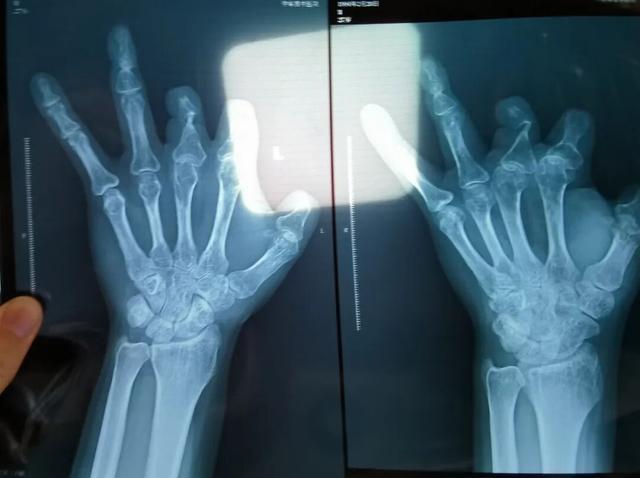

患者王海森左手拇指关节以上部位被电锯切断,收费单显示术中使用了微血管吻合装置,但X光片中未显示该器械。新京报记者 程亚龙 摄

单价1.68万元,声称在术中植入体内、用于缝合血管的两个环形吻合装置,竟然在王海森的X光片上消失了。

该产品的代理商曾向新京报记者证实,微血管吻合装置为植入型医疗器材,患者拍摄X光片时会有显示。新京报记者获取了一位曾在郑大一附院接受手术、使用了该产品的患者的X光片,其手术部位可见一绿豆大小的光圈。

装置上带有不锈钢针,不可能被人体吸收,唯一的可能就是“手术时其实没有使用”。尽管之前也有其他人向王海森透露过这一点,但直到看到片子前,他一直都不相信。